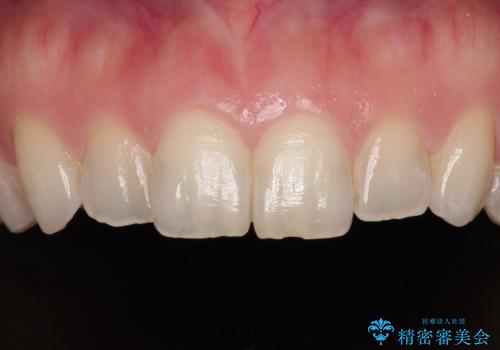

当初は奥歯のみの治療をご希望でしたが、話を進めていくうちに、軽度ではあるものの、幼少期の薬の影響で歯が変色していることがコンプレックスであるということが分かりました。

長年歯の色が塞ぎ込んでいた部分があるとのことで、これを機会に全ての歯を真っ白にするために、オールセラミッククラウンにて補綴治療を行うこととしました。

より白さが目立つように、自然な仕上がりではなく、作り物の雰囲気があるフルジルコニアクラウンにて補綴治療を行いました。